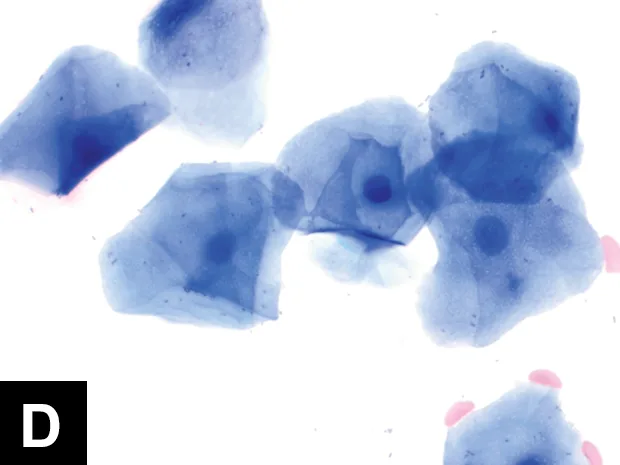

Six types of cells typify vaginal cytology: parabasal cells (A), which look like small, O-shaped oat cereal pieces; small intermediate and large intermediate cells (B), which look like fried eggs; superficial (“cornified”) (C) cells, which look like corn flakes; neutrophils; and red blood cells.

Estrus (receptive, fertile): Superficial cells predominate and their nuclei become pyknotic or absent/anuclear (D, E).